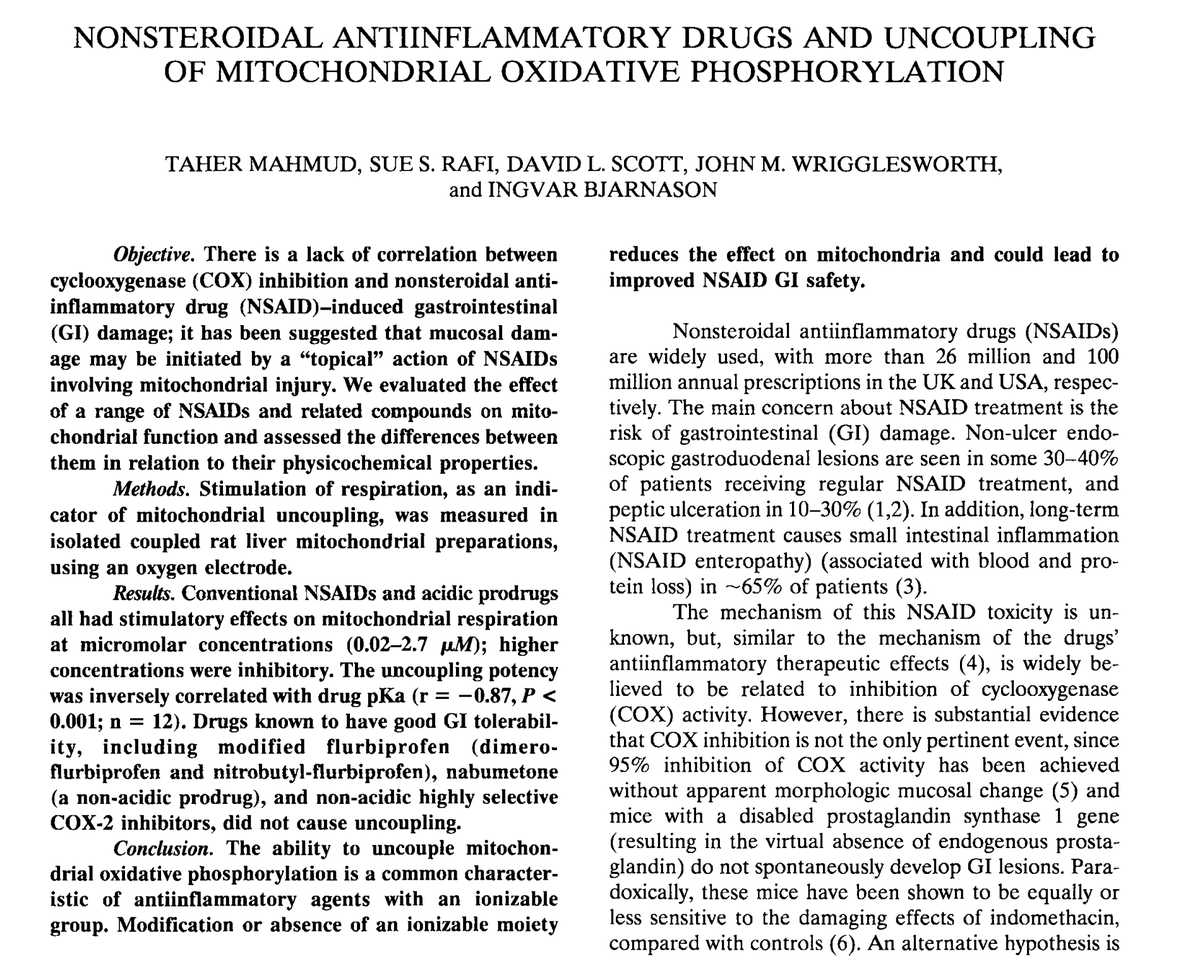

Aspirin’s ability to counteract tiredness is related to its ability to stimulate mitochondrial energy production at low doses (baby aspirin).

The main aspirin metabolite, salicylic acid, also prevents the structural and functional breakdown of the mitochondria over time.

Importantly, at very high doses (multiple grams), aspirin tends to actually suppress mitochondrial energy production, the opposite of what it does at the lower doses (<160 mg).

Some like the higher doses for specific reasons, like cancer, or for more potent blood sugar or anti-stress effects.